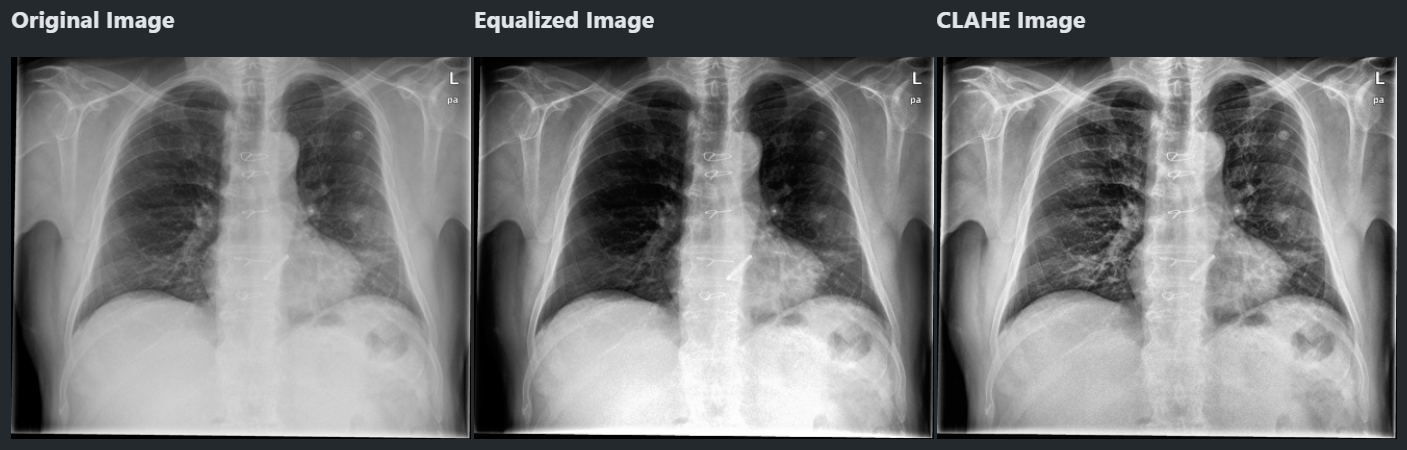

CLAHE 히스토그램 균일화

- 그래서 준비했습니다 CLAHE 히스토그램 균일화

- 이미지를 여러 개의 타일로 나누어 타일마다 균일화

- 노이즈가 있을 수 있으므로 제한을 넘는 값은 모든 영역에 균일하게 배분

1 2 3 4

clahe = cv.createCLAHE( clipLimit=2.0, # 밝기 제한을 설정. 보통 2.0-4.0 tileGridSize=(8, 8)) # 이미지를 가로 8개, 세로 8개의 타일 -> 총 64개로 나눔 clahed = clahe.apply(src)

- 이제 좀 특징이 잘보이지